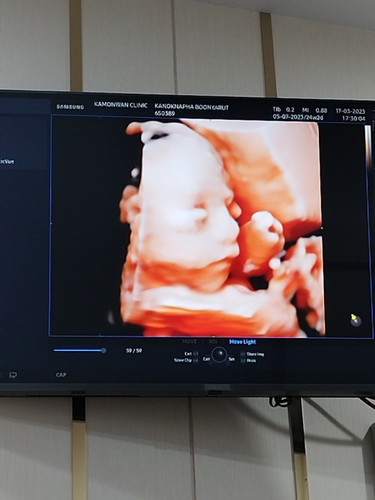

เเม่ๆบ้านไหนท้องเล็กบ้างค้ะเเบบเล็กเรยเเต่ลูกดิ้นเเละน้ำหนักตามเกณบางทีก็กังวล บ้านนี้26w3d